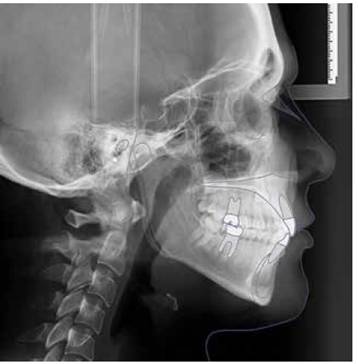

Estudio retrospectivo realizado en pacientes en tratamiento de ortodoncia en la Clínica Odontológica de la Universidad Andrés Bello. El estudio se basó en la comparación de las características de la radiografía inicial (previa al tratamiento) de dos grupos pareados (por edad y sexo), grupo estudio y grupo control.

El estudio se basó en medidas obtenidas de teleradiografías laterales de cráneo, las cuales cumplieron los siguientes requisitos: posición natural de cabeza, máxima intercuspidación (MIC) y labios en reposo.

Las variables cráneofaciales evaluadas fueron basadas en puntos y líneas cafalométricas ( tabla I ) de distintos análisis cefalométricos, estos análisis fueron realizados por un solo operador en forma manual, para posteriormente ser cotejados por un segundo operador.

Trazado medidas

Trazado RX